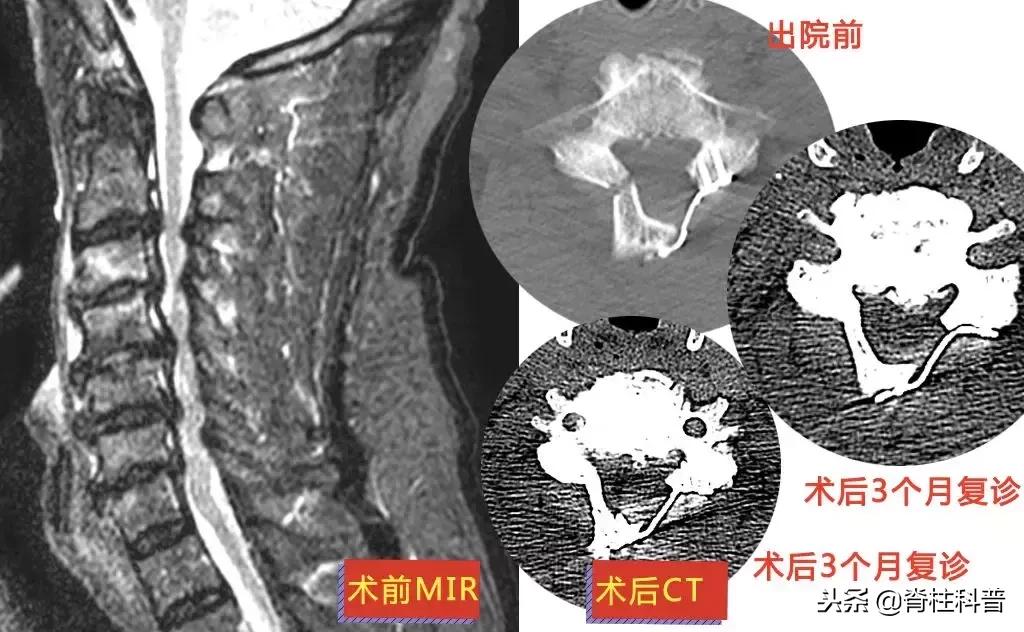

这其中来自茂名市48岁的李三姨(化名)最为典型。

这10多年来,李三姨的左颈、肩背部反复酸痛,休息、热敷甚至是止痛药治疗时可缓解。但是来院就诊前1个月,突然出现左上肢放射性疼痛,于是在2018年8月28日前往当地医院诊治。医生予以中药、针灸治疗,但无效。

10天后,再次予以颈椎牵引治疗,症状稍缓解,可是颈痛发作频繁。经过熟人介绍,特意从茂名来到广州南方医科大学第三附属医院,找到张忠民主任医师治疗。在2018年9月20日在门诊被主任以“神经根型颈椎病”收治入院。10月3日手术,术后疼痛症状得到明显改善。

▲ 李三姨:术前MRI与术后X光